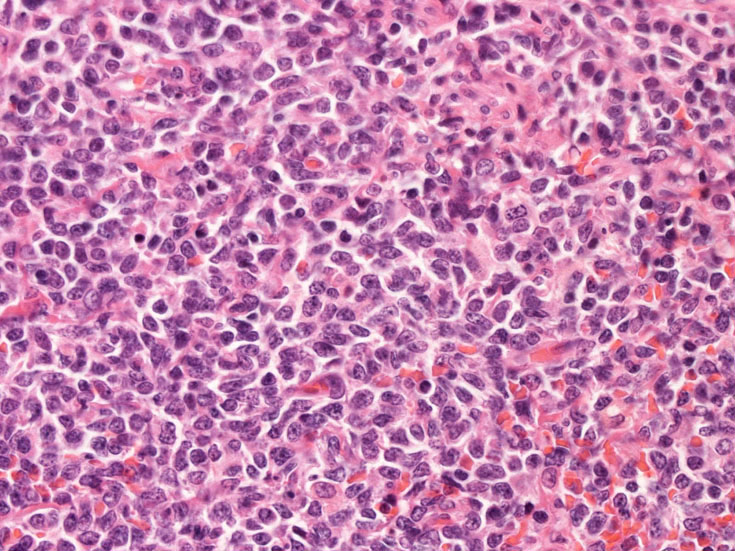

Fig04, Fig05は腫瘍細胞の拡大像。大型異型細胞の出現が認められる。腫瘍細胞はCD4+, CD56+, CD123+(Fig.06)

tcells02.jpg

Fig.04Fig.05Fig.06 CD123